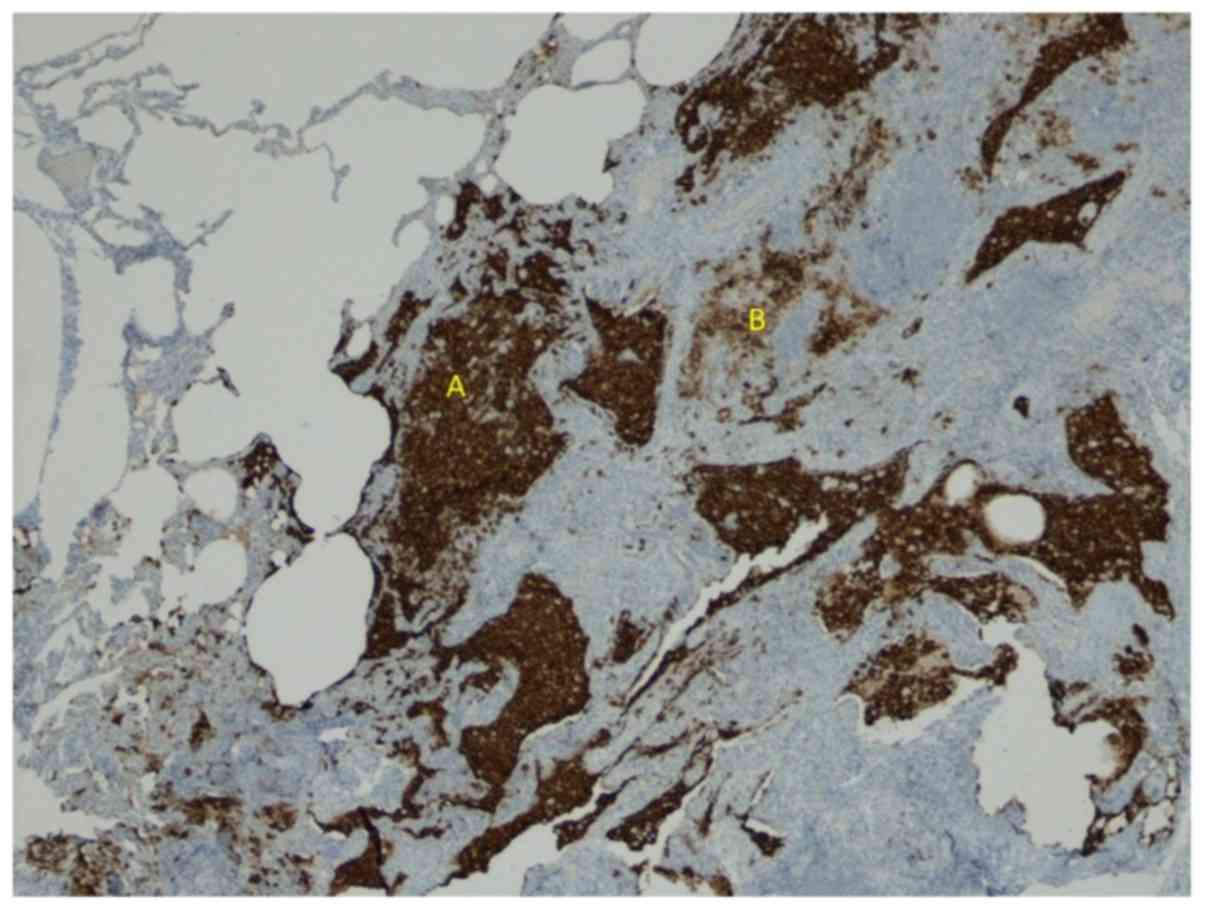

Pulmonary Langerhans cell histiocytosis (PLCH) is a rare sporadic cystic lung disease of unknown aetiology that is characterised by the infiltration and destruction of the wall of distal bronchioles by CD1a+Langerhans-like cells. In adults, PLCH is frequently isolated and affects young smokers of both sexes.

Introduction. Langerhans cell histiocytosis (LCH) is a rare disorder of unknown aetiology that is characterised by the infiltration of involved tissues by dendritic cells sharing phenotypic similarities with Langerhans cells, which are often organised into granulomas [1].

HRCT is mandatory for every suspected case of PLCH [ 8, 9 ]. It can visualise parenchymal lesions, such as nodules or cysts that are not readily visible on standard chest radiography. The typical HRCT pattern combines small, poorly limited nodules, cavitated nodules and thick- and thin-walled cysts predominantly in the upper and middle lung fields, with a relative sparing of the bases. The lesions are focal and are separated by apparently normal parenchyma, and they affect both the peripheral and the central parts of the lung fields.